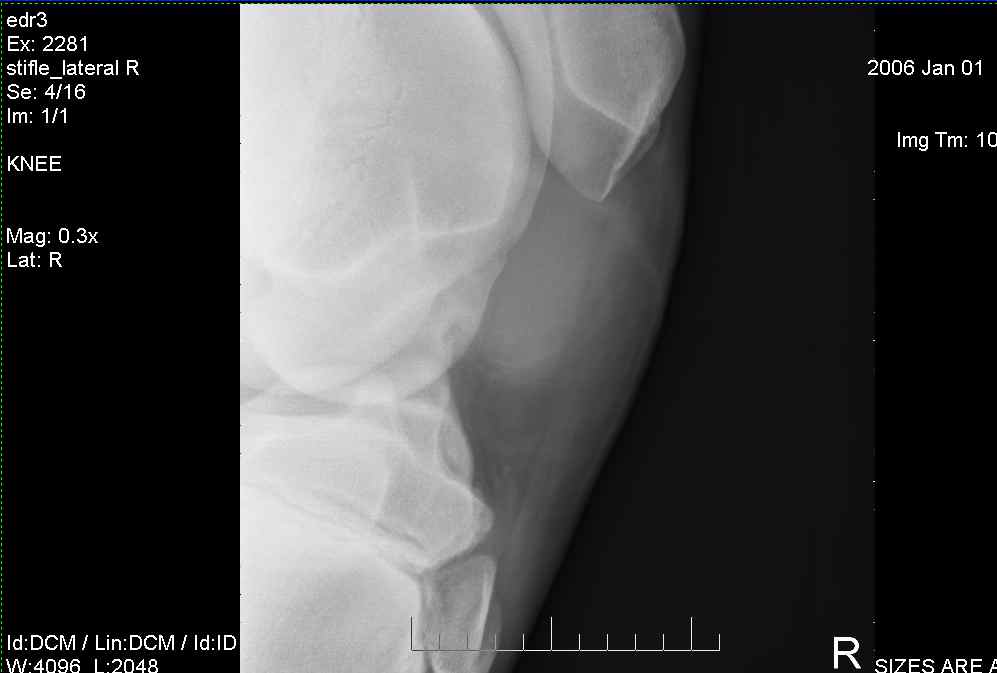

These are x-rays of my 5.5 month old Oldenburg filly, who came up grade 1 lameness in Right Hind stifle. She was diagnosed w/OCDs in both stifles, and recommended surgery when she is 8 mo old. What do you think her prognosis is? How bad are the OCDs, and what do you think her chances of recovery are? Is it good advice not to breed her when she gets older? Her sire, nor dam have a history of producing OCD babies, but this filly has been very large since birth. Are there any supplements I can give her to help improve her condition while we wait to do surgery? thanks much for your comments...

Right stifle-1

Right Stifle-2

Right Stifle-3

Right Stifle-4

I am sorry to meet you over such a serious problem. I am currently traveling so don't have access to my library where I might be able to provide you with more precise prognostic information but the OCD lesions on the trochlear ridges of both stifles are remarkable and often result in chronic lameness with secondary DJD of the stifles. Therefore surgery would be recommended and the prognosis from the radiographs alone would be guarded for future athletic potential but should really wait until the arthroscopic surgery when a better idea of the pathology in the joint can be better characterized. The horse should not be bred because of genetic predisposition for such lesions. Is there effusion (swelling) in the stifle yet?

This is how my vet explained the xrays to me: On the first xray, look at the top-left bone (femur). The bottom of it should have a smooth curve going all the way around, but the bottom of the femur shows up darker on the xray, and the edge is sheared off. This lesion is less dense (softer) than the rest of the bone. In surgery, they would take out the lesion (all of the damaged area), and fill it back in new material. The first 4 pics are her right stifle, the last three pics are her left stifle. On the first pic of her left stifle (fifth picture in the post) look at the bottom edge of the bone on the top right. Again, you can see the damaged edges. On the last pic, I think there is another area of OCD showing up on the top-right side. Maybe Dr. O. can better clarify the areas we are looking at if I am incorrect, or if I am missing anything else.